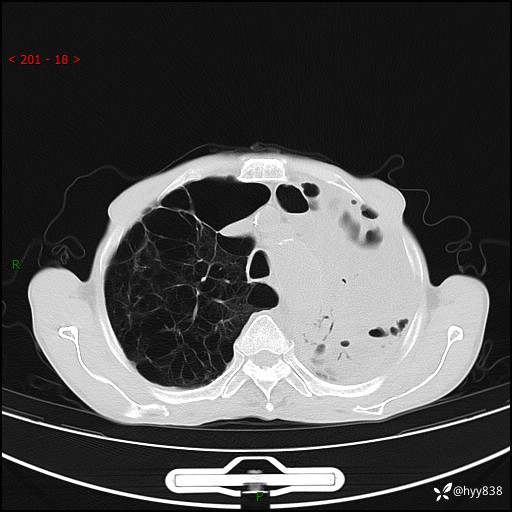

老年男性,反复咳嗽、咳痰、气喘10余年,再发3天。大叶性实变+胸膜病变-结果公布

胸部CT平扫+增强